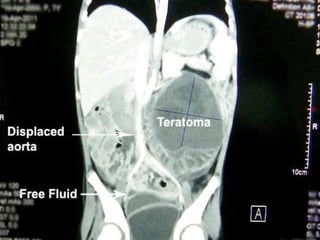

Teratoma

• Germ cell tumor

• Less than 10% of teratomas are

found in the retroperitoneum.

• The third most common tumor in the retroperitoneum in

children, after neuroblastoma and Wilms tumor

• More common in females, with a bimodal age distribution (<6

months and early adulthood).

• Mature teratoma (dermoid cyst) contains well-differentiated

tissues from at least two germ cell layers.

• Mature teratomas are predominantly cystic.

• Calcification (toothlike or well defined) and fat can be seen in

56% and 93% of cases, respectively

T2- MRI: Mature teratoma with fat fluid

level and calcification

Retroperitoneal Teratoma